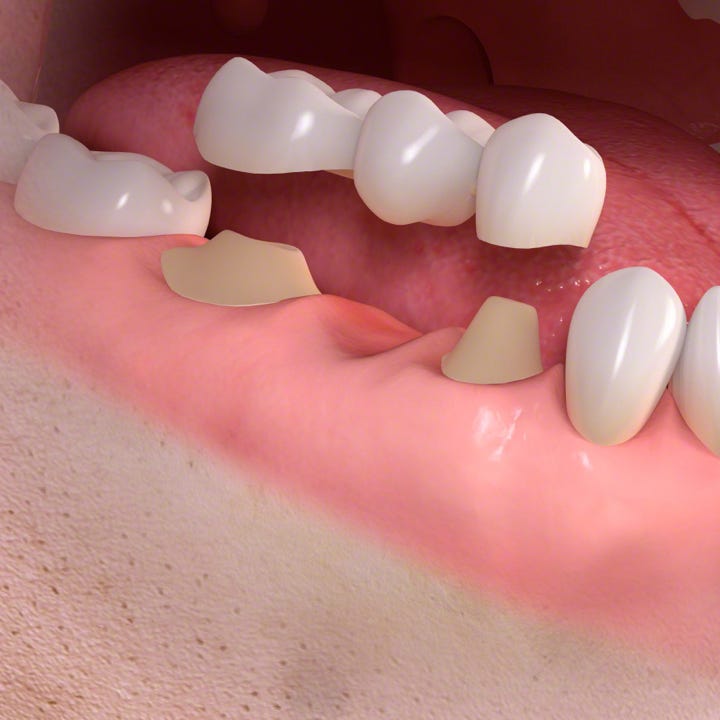

Keramische Kronen und Brücken

Ist ein Zahn einmal so stark zerstört, dass er nicht mehr mit einer Füllung oder einem Inlay versorgt werden kann, lässt sich diesem meist mit einer individuell angepassten Krone zu neuem Glanz verhelfen.

Fehlt ein Zahn und ein Implantat lässt sich nicht inserieren oder ist nicht gewünscht, kann in der Regel auch mit einer Brücke versorgt werden.